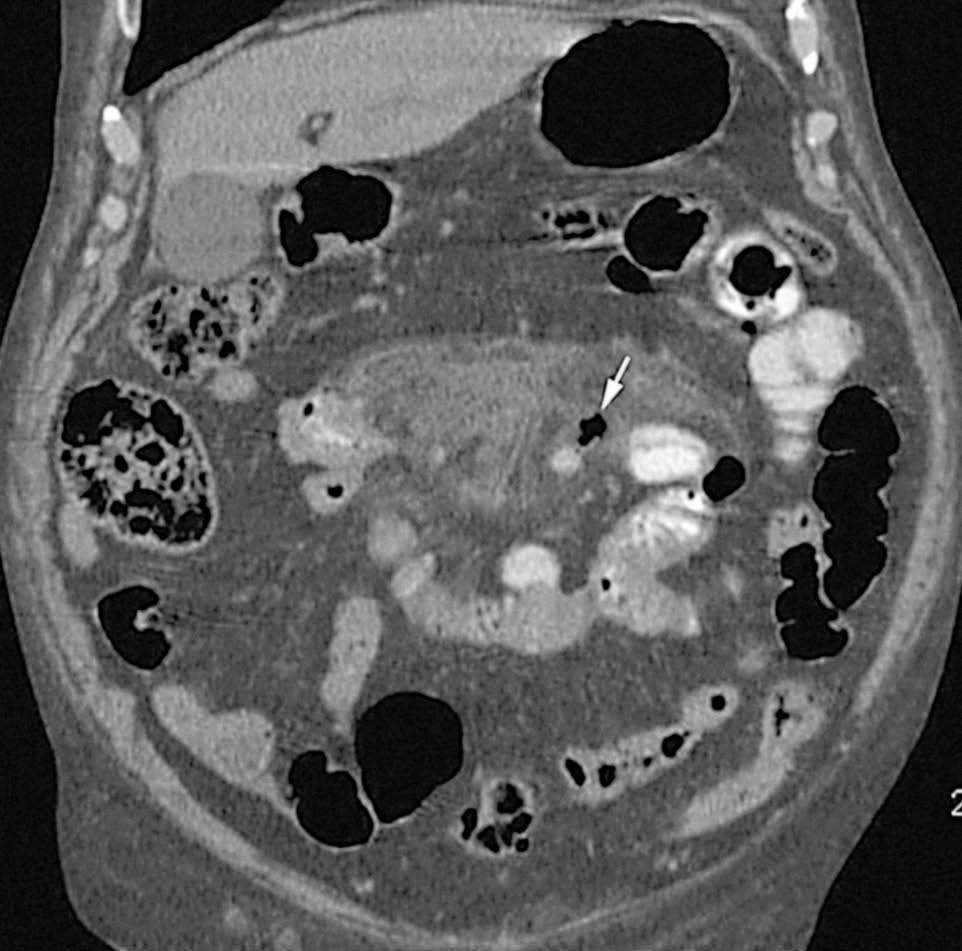

Fig. 1. Reconstrucción multiplanar (MPR) coronal que pone de manifiesto los cambios inflamatorios de la grasa mesentérica adyacente al asa yeyunal afectada y el aire libre en íntimo contacto con uno de los divertículos (flecha).

Sr. Director: Presentamos el caso clínico de un paciente varón de 86 años, con antecedentes de cardiopatía isquémica, hipertensión arterial bajo tratamiento médico, enfermedad pulmonar obstructiva crónica con disnea basal a medianos esfuerzos, anemia crónica ferropénica, diverticulosis de sigma diagnosticada mediante enema opaco realizado para estudio de la anemia, hiperlipemia, insuficiencia renal crónica leve y síndrome prostático secundario a hiperplasia benigna de próstata. Consulta por cuadro de dolor abdominal generalizado de rápida aparición, acompañado de náuseas y sensación distérmica no termometrada. En la exploración física llama la atención la presencia de un abdomen distendido con signos de irritación peritoneal. En la analítica de urgencias destaca la presencia de anemia (hemoglobina, 8,3 g/dl; hematocrito, 25%), insuficiencia renal (creatinina, 3,5 mg/dl), hiperpotasemia (potasio, 6,7 mEq/l) y leucocitosis (14.200/µl). En la radiografía de abdomen sólo destacaba una discreta dilatación de algunas asas de intestino delgado. Dado el contexto clínico del paciente (edad avanzada y enfermedad cardiopulmonar asociada) se solicita una tomografía computarizada (TC) abdominal urgente para completar el diagnóstico, ante la posible necesidad de intervención quirúrgica. Se realizó una TC multicorte (TCMC) de abdomen con contraste oral, pero sin contraste endovenoso (debido a la insuficiencia renal del paciente), en la que se observó una dilatación y engrosamiento de la pared de asas intestinales yeyunales que presentaban múltiples divertículos, asociado a una afección inflamatoria de la grasa mesentérica adyacente y discreta cantidad de aire libre extraluminal en íntima relación con uno de los divertículos yeyunales (fig. 1). Asimismo, se visualizaron pequeños divertículos en sigma no complicados.

El interés de este caso clínico es que se pudo realizar del diagnóstico preoperatorio de certeza mediante TC abdominal dada la clara visualización del divertículo perforado en las imágenes tomográficas, a pesar de la ausencia de contrate endovenoso, y como ejemplo de otra causa infrecuente de abdomen agudo a tener en cuenta en pacientes de avanzada edad.